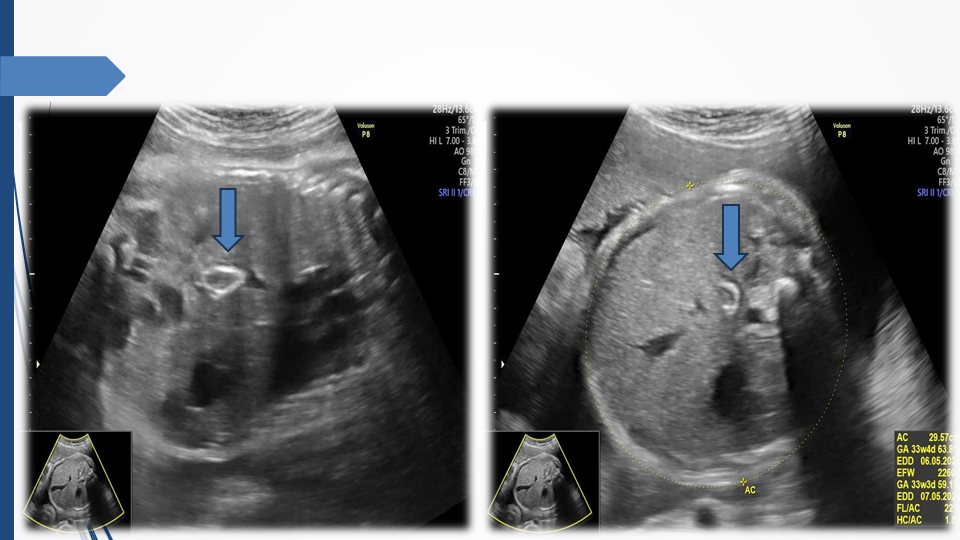

Tầm soát chủ động bất thường dây rốn và tuần hoàn thai để giảm thiểu nguy cơ thai lưu đột ngột - Báo cáo loạt ca hiếm gặp và khuyến nghị thực hành